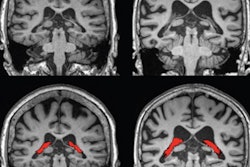

The researchers found that, overall, the MRI-based deep-learning model had a high accuracy of distinguishing between control exams and those exams that showed Alzheimer's indicators, with an area under the receiver operating curve (AUROC) of 0.973. The maps the model generated focused on the hippocampus, the area of the brain where Alzheimer's disease pathology manifests.